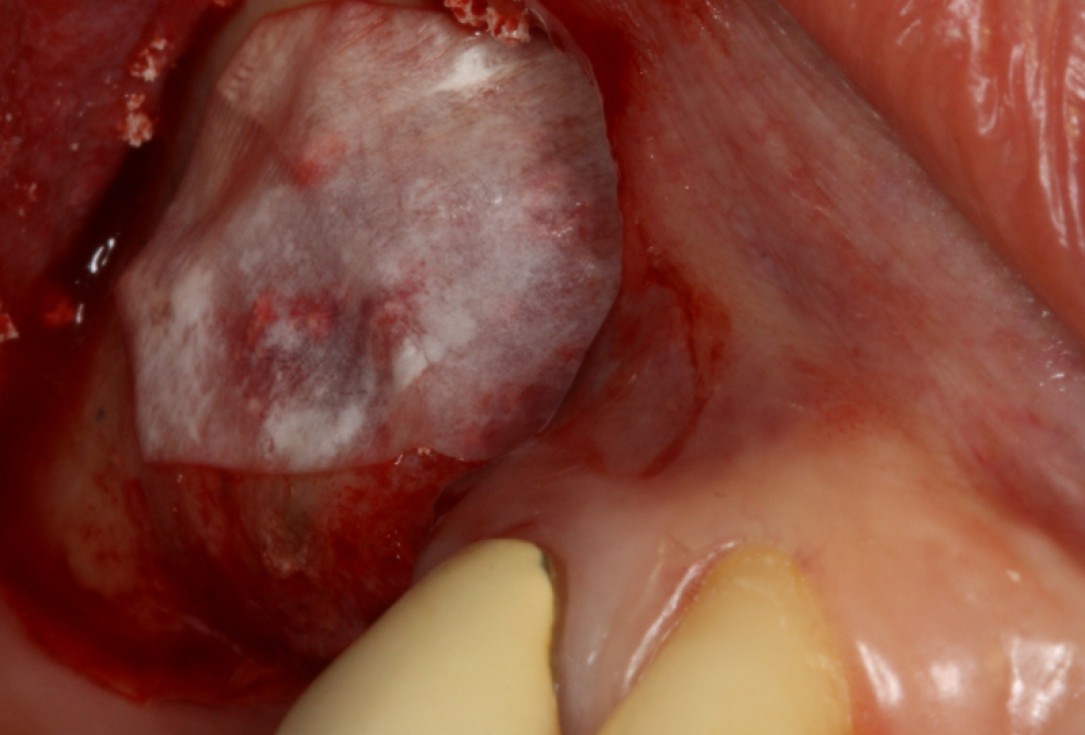

08/20 - Surgical presentation of the alveolar ridgeGBR with maxresorb® & Jason® membrane - Prof. Dr. Dr. D. Rothamel

-